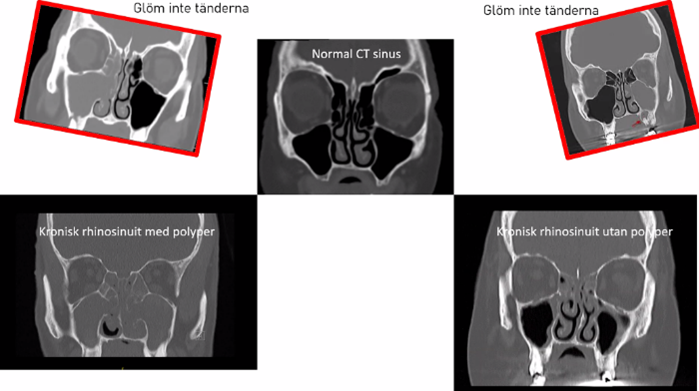

CT (ska vara svart i bihålor = luft)

• Nere till vänster är proppfull med polyper

• 40-årig man, illaluktande högersidig snuva och värk höger kind sedan 1 år

o Ofta spolning men tandläkare är viktigast. Klindamycin eller penicillin + flagyl kan man använda

Vilken bild är troligen den 40-årige mannens? Vad beror ofta en ensidig bihåleinflammation på?

A

Uppe vänster

Tandinfektion!